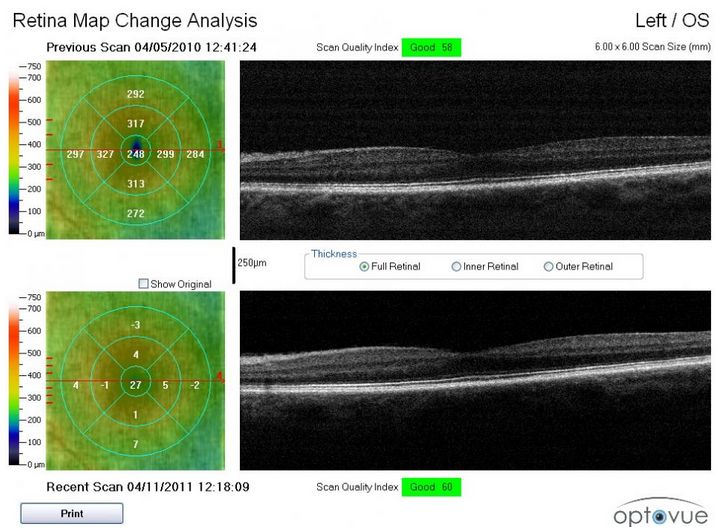

- automatyczna analiza i raport zmian w czasie

- automatyczna analiza i raport asymetrii oczu dla grubości siatkówki